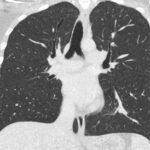

Paciente femenina de 26 años de edad, sin antecedentes patológicos de relevancia, sin dosis de vacuna BCG. Cursa con cuadro clínico de ocho meses de evolución, caracterizado por dolor en región pectoral izquierda intermitente, que se exacerba a la inspiración profunda. En el último mes se palpa masa indurada dolorosa a la palpación a nivel del cuadrante inferior interno de mama izquierda, motivo por el cual se realiza ecografía de partes blandas, donde se observa a nivel retropectoral en íntimo contacto con la parrilla costal imagen hipoecogénica de bordes delimitados, avascular al Doppler color por lo cual se solicita TC de tórax con EV. En ella se observa en topografía del cuarto espacio intercostal, imagen hipodensa con realce periférico tras la administración del contraste que desplaza por efecto de masa el parénquima pulmonar adyacente y se proyecta a la pared torácica anterolateral izquierda; mide 40 mm x 55 mm. Además, se visualiza otra imagen de similares características de base pleural en contacto con el octavo arco costal posterior izquierdo que mide 6 mm x 11 mm.

Los estudios de imagen, especialmente la radiografía de tórax y la tomografía computarizada (TC), tienen un papel importante en el diagnóstico de la tuberculosis pleural, ya que la radiografía de tórax nos permite identificar el derrame pleural, la afectación unilateral y posibles consolidaciones pulmonares. En fases avanzadas, también puede mostrar engrosamiento pleural o secuelas fibrosas.

La tomografía computarizada proporciona información más detallada sobre el compromiso extrapulmonar, revelando ganglios linfáticos mediastinales aumentados o nódulos subpleurales que sugieren focos de infección activa.